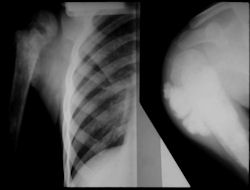

Gross Pathology: Osteosarcoma of Proximal Humerus

- originates from metaphysis of the proximal humerus, extends into surrounding soft tissues

- large soft tissue component that is crossing the glenohumeral joint

- was removed via an extra-articular resection, including scapula (Tikhoff-Linberg resection)

Examples of radical limb sparing surgeries for osteosarcomas in various anatomic locations (distal femur, proximal tibia, proximal humerus, scapula)

In each case, the tumor and bone from which it arose were resected. This required meticulous dissection, mobilization and preservation of adjacent pertinent neurovascular structures. In each case presented here, the defect was reconstructed with a special modular segmental tumor prosthesis. This also replaces the adjacent joint in many instances.

Proximal Humerus: Radical Limb Sparing Extra-Articular Resection and Prosethetic Reconstruction